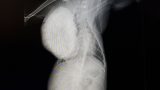

猫には前例がないほどの大きな骨肉腫で、放っておくと肺が圧迫され息ができなくなり亡くなってしまいます。

検査、CTで約14万円、手術や入院で約50万円。腫瘍、肋骨を取る大きな手術になります。手術後の経過によってはそれ以上かかることもあるそうです。根治は難しいそうですが、少しでも長く生きて最期は幸せにしてあげたいと思っています。